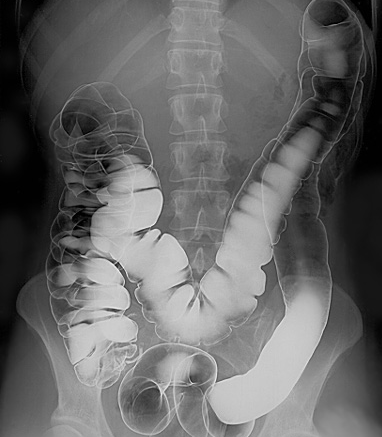

A barium enema is a rectal injection of barium contrast. This coats the lining of the colon and rectum and X-ray films are obtained under fluoroscopic control. Air introduced into the large bowel may be used to give a double-contrast technique. Barium enemas are performed much less often than in the past because of the increasing use of colonoscopy and CT colonography.

Intestinal tract barium enema

© Glitzy queen00 at English Wikipedia., Public domain, via Wikimedia Commons

Abnormalities detected include large bowel obstruction, tumours, ulcers, diverticular disease, inflammatory bowel disease, intussusception, Hirschsprung's disease and thickening of the lining of the colon or rectum.

Barium is run into the colon under gravity and radiographs are taken. Air is also then introduced into the rectum for a double-contrast barium enema.